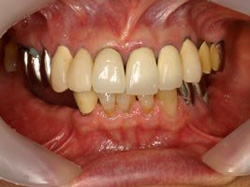

両側5歯症例

両側5歯症例両側5歯症例両側5歯症例 主訴-義歯のバネが壊れて手前の歯が痛んできた。 術前(旧義歯装着、鏡像) 術前(下顎粘膜面、鏡像)術前(下顎粘膜面、鏡像)術前(下顎粘膜面、鏡像) 術前レントゲン術前レントゲン術前レントゲン 術前口腔内(正面観)術前口腔内(正面観)術前口腔内(正面観)

術後(鏡像)術後(鏡像)術後(鏡像) 術後口腔内(正面観)術後口腔内(正面観)術後口腔内(正面観)もう入れ歯は要らなくなりました。 術後レントゲン術後レントゲン術後レントゲン